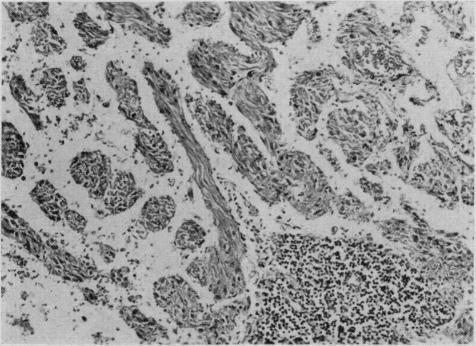

Pulmonary and lymph node myomatosis: review of the literature and report of a case.

Can Med Assoc J. 1967 Feb 18;96(7):420-4.